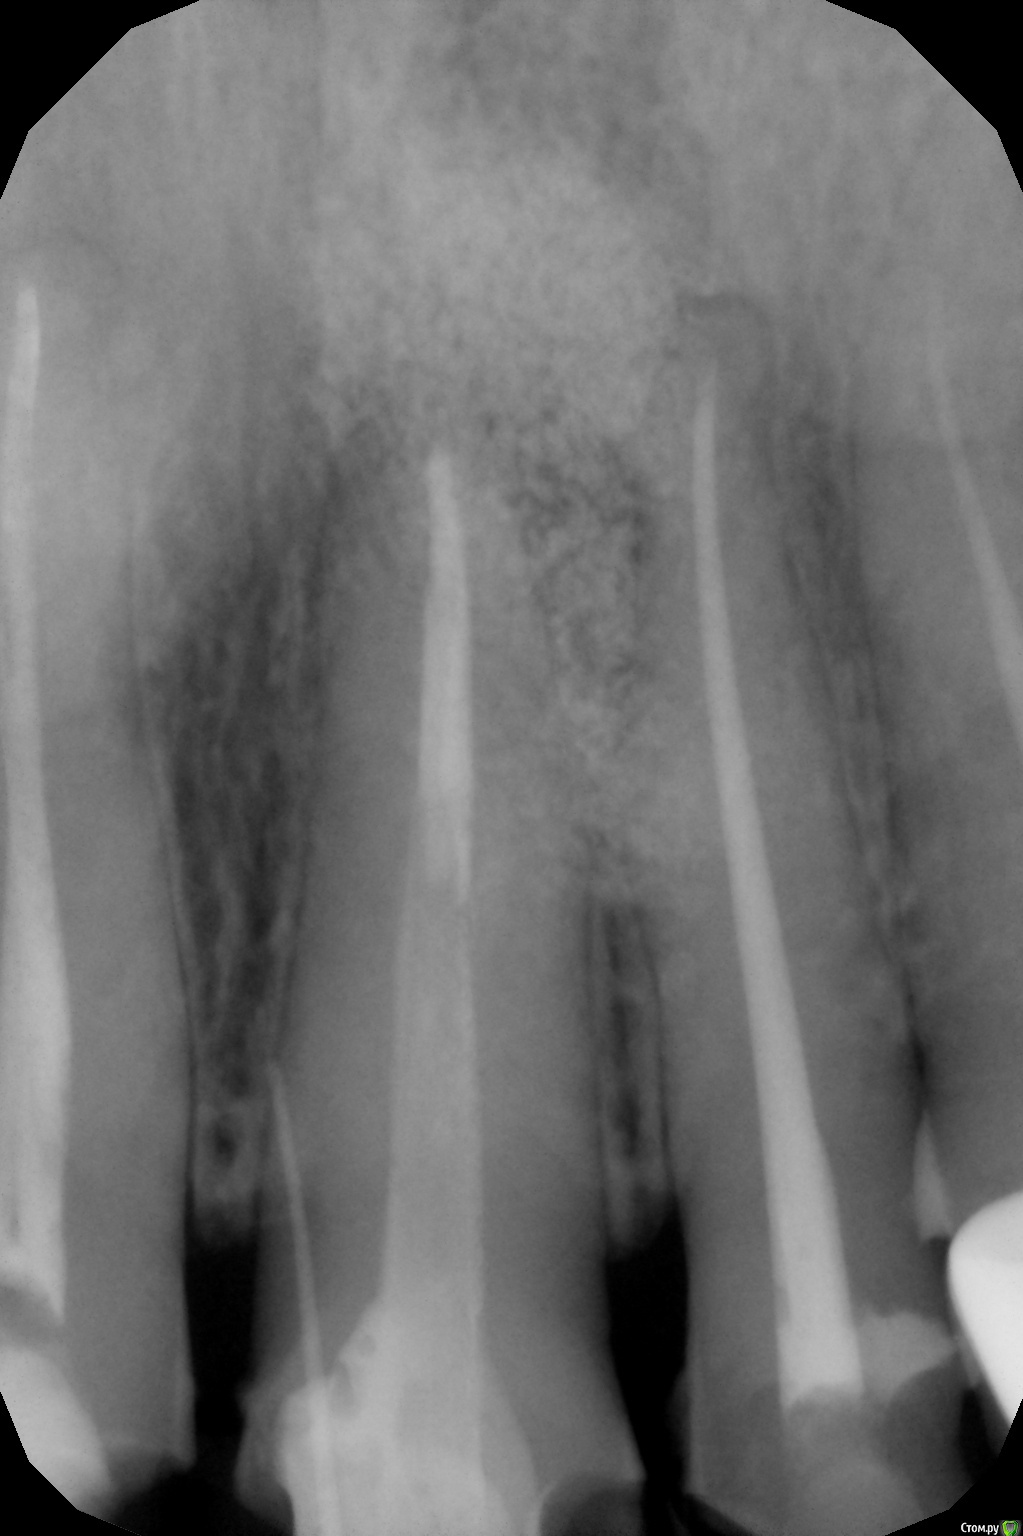

Vilka Опубликовано 17 мая, 2018 Поделиться Опубликовано 17 мая, 2018 Добрый день уважаемые специалисты. Моя история: http://forum.stom.ru/topic/30641-rezektciia-21-zuba/http://forum.stom.ru/topic/31532-oslozhneniia-posle-rezektcii-izlishki-kostnogo-ma/ Если кратко: у меня опять рецидив кисты на единичке слева. На десне образовалось уплотнение, терапевт, сделав снимок, сказала, что это свищ, но кисту не видит. Отправили на КТ, посмотрев его хирург, который проводил резекцию, сказал, что киста сбоку корня (но где именно не знаю, так как с этим врачом мне пока пересечься не удалось). Вердикт: зуб удалять. Ну или опять резекция. В другой клинике кисту сбоку не видят, видят ее сверху, где темное пятно. В этой клинике зуб также советуют удалять. Врач, который проводил резекцию ранее мне объяснял, что темное пятно КТ это пустота, которая образовалась из-за удаления излишков биоса - на предыдущих кт это пятно уже было. Вопрос: удалять в любом случае? Срез смогла сделать только такой.Ссылка на КТ https://ru.files.fm/u/7zzyga5n Заранее всем спасибо. Ссылка на комментарий